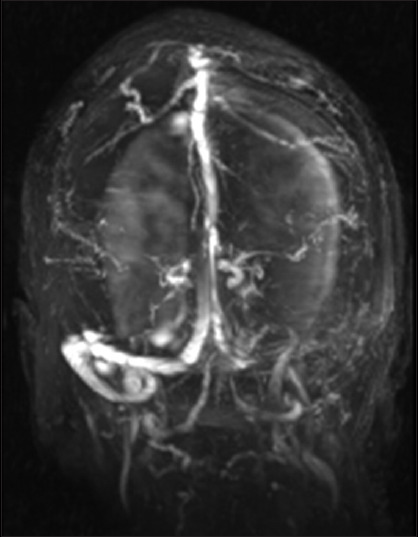

Abstract Image